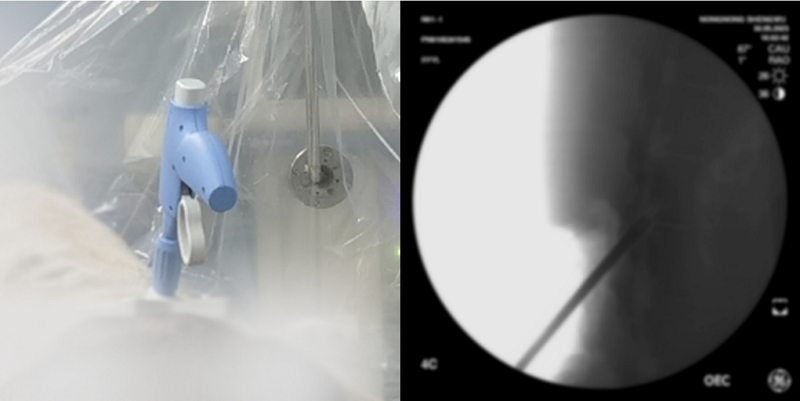

在覆蓋疼痛患者多、手術(shù)量大的微創(chuàng)介入領(lǐng)域,新云醫(yī)療自主研發(fā)出國內(nèi)首款針對(duì)腰椎管狹窄癥(LSS)的微創(chuàng)手術(shù)器械套件NewMild,將為黃韌帶肥厚型LSS提供更優(yōu)術(shù)式。該微創(chuàng)手術(shù)僅需一個(gè)微小的切口即可切除多余韌帶,從源頭上治療LSS,且具有類似于硬膜外類固醇注射的安全特性,患者通常在手術(shù)24小時(shí)后便可自由活動(dòng),在縮短患者康復(fù)期的同時(shí)也減輕其經(jīng)濟(jì)負(fù)擔(dān)。

利用NewMild開展腰椎管狹窄癥微創(chuàng)減壓手術(shù)